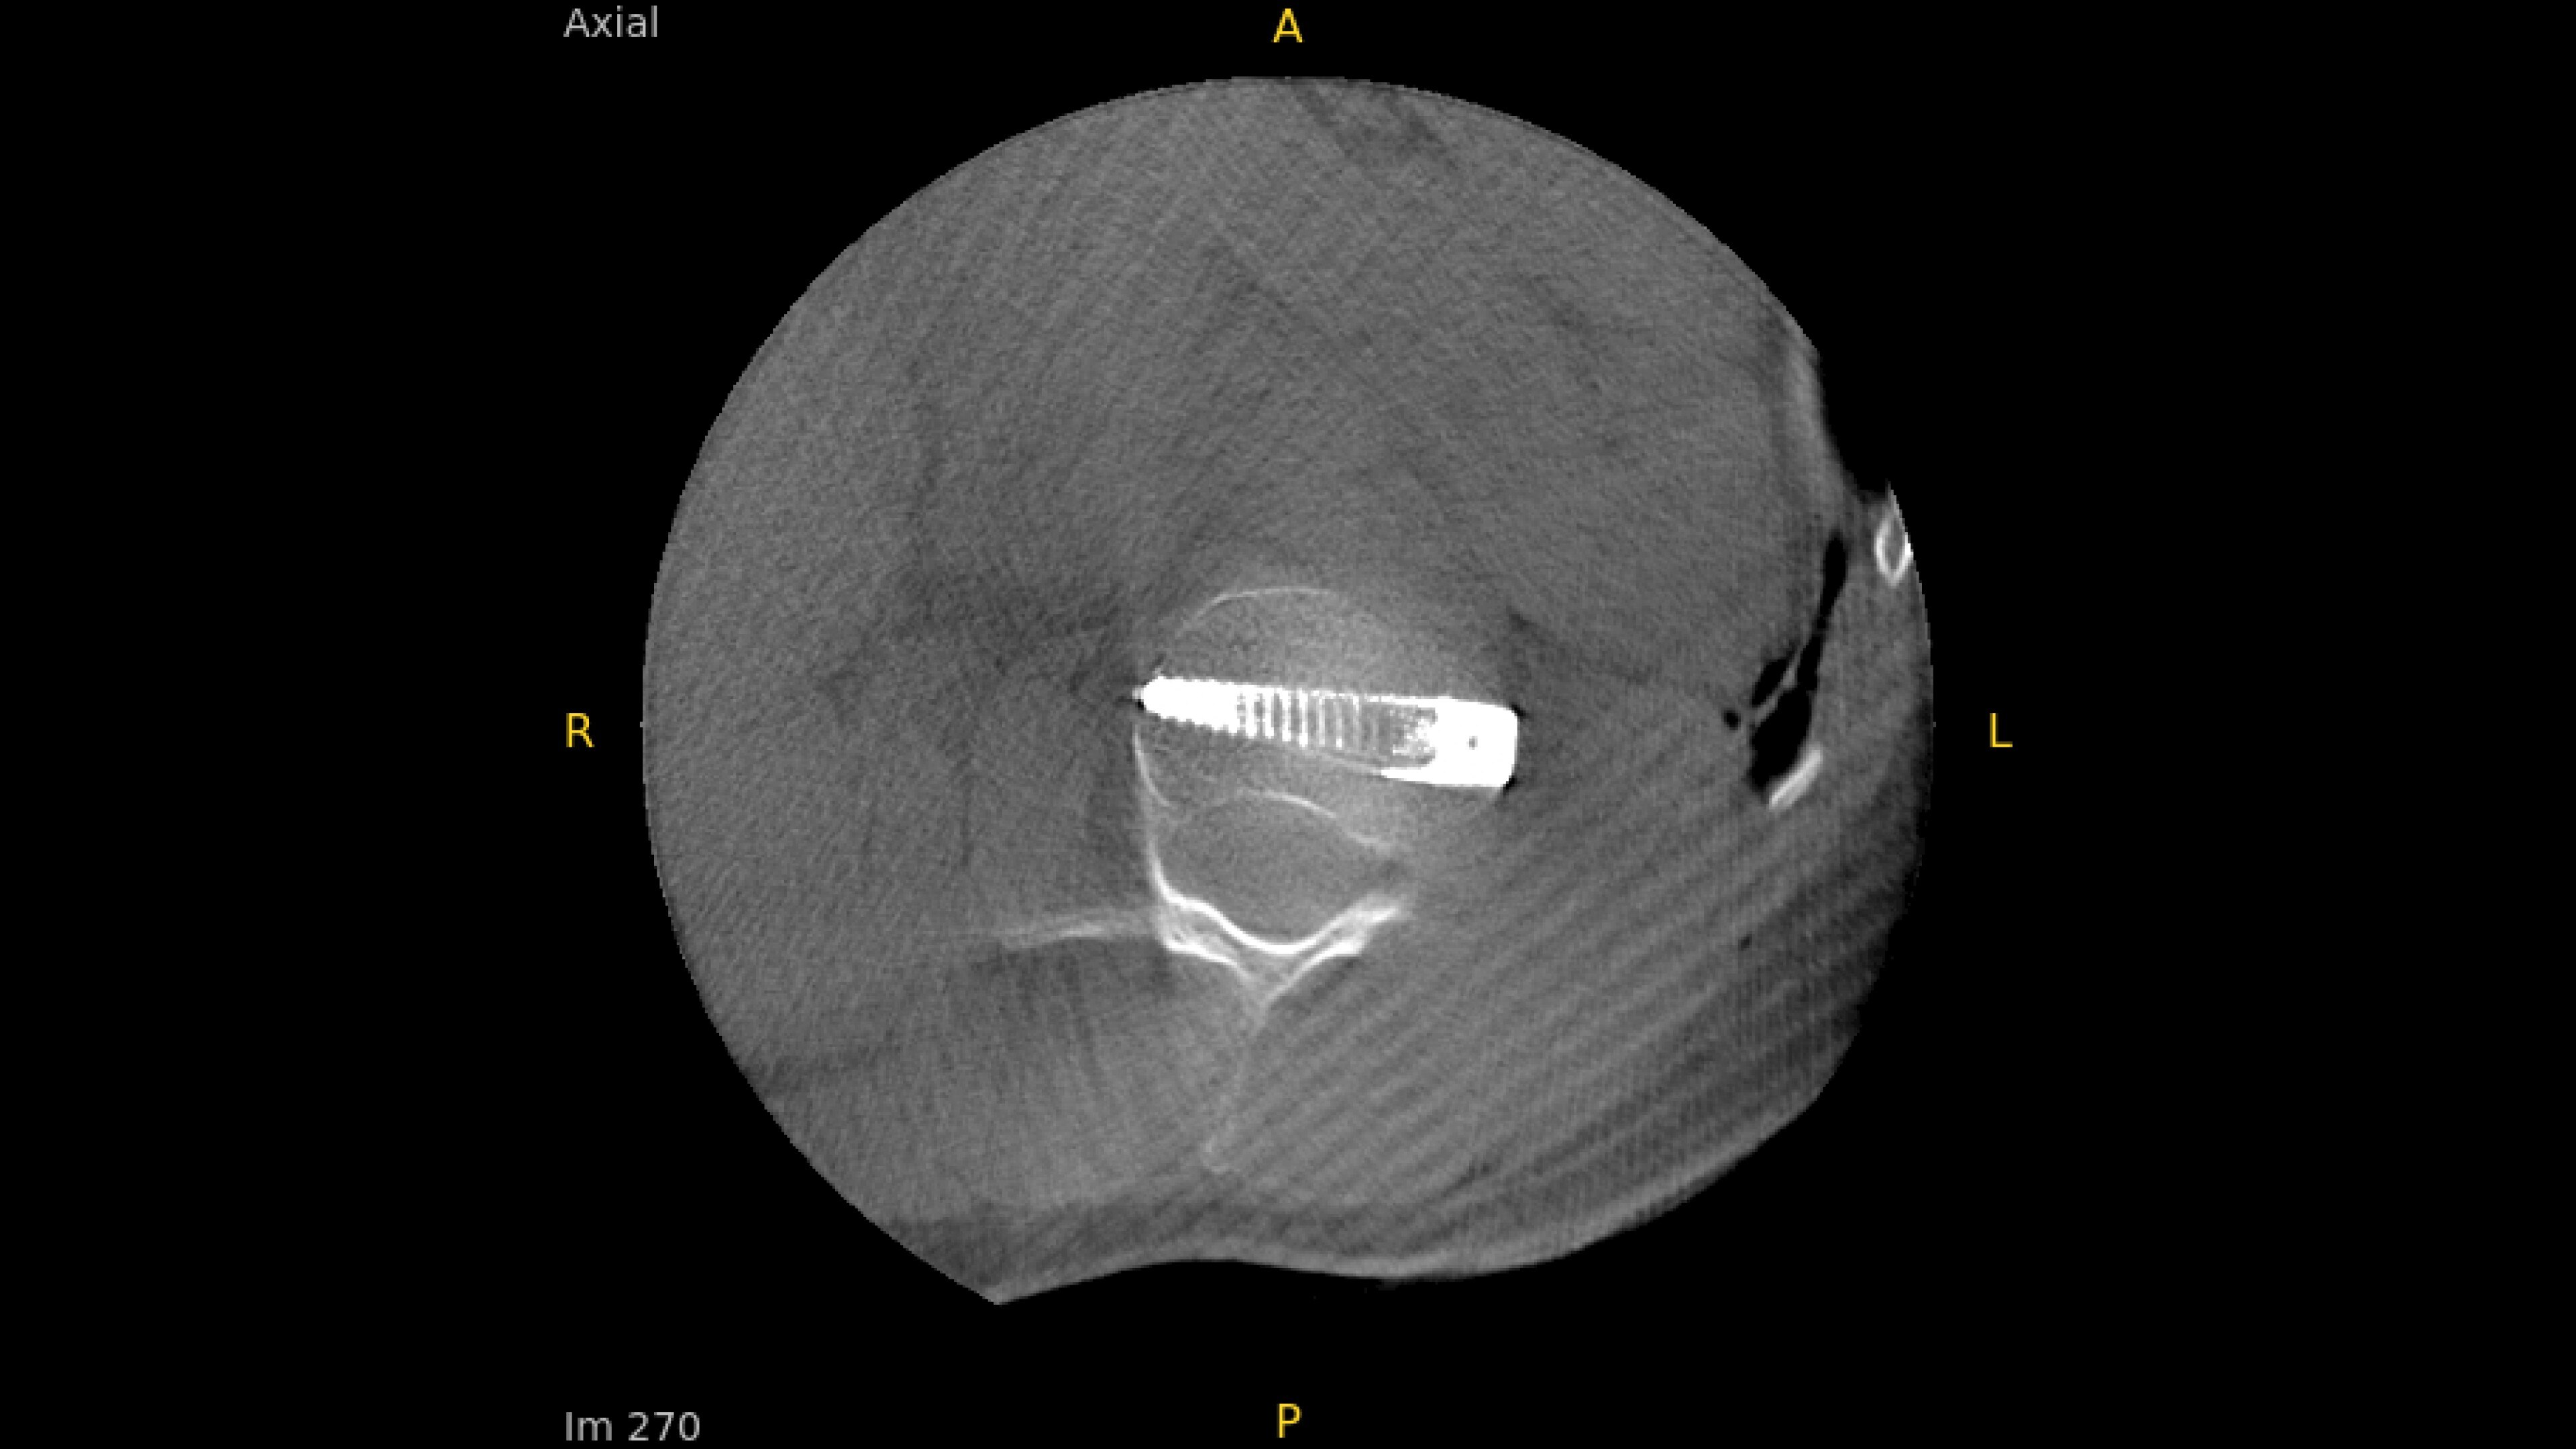

With OEC 3D, comprehensive imaging coverage of 19 cm x 19 cm x 19 cm 3D volumes and exceptional 2D images enables viewing several levels of the spine in the operating room.

The OEC 3D presents five perspectives: Axial, Coronal, Sagittal, MIP, and VR, on a 4K display for clear and detailed review of 3D volumes and 2D images